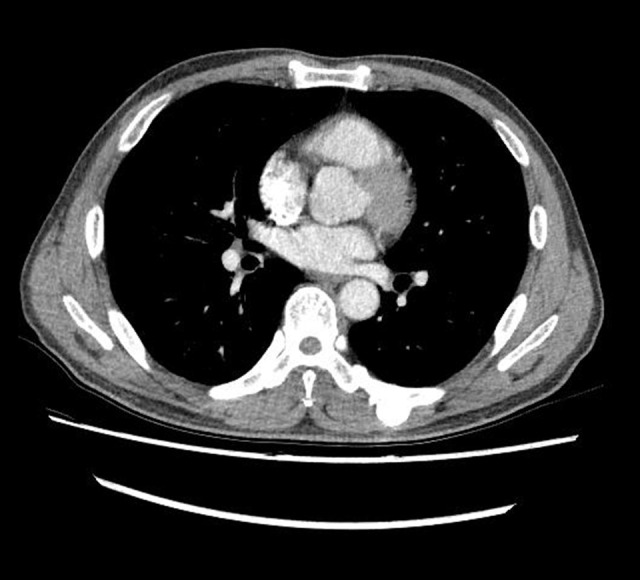

Pre-training data. We use the same dataset as LLaVA-Med (llava-med). Stage 1 includes 600K image-text pairs filtered from PMC-15M, converted into instruction-following data with simple image descriptions. Stage 2 comprises 60K image-text pairs from PMC-15M across five modalities: CXR, CT, MRI, histopathology, and gross pathology. GPT-4 is then employed to generate multi-round Q&A in a tone mimicking visual interpretation, converting these pairs into an instruction-following format.